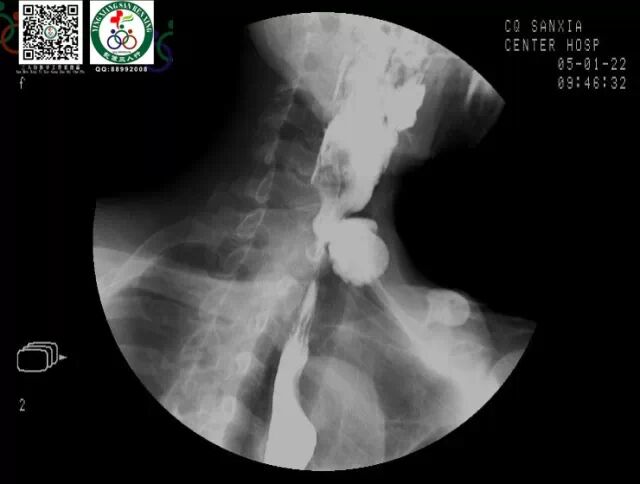

上消化道钡餐造影检查

图片尺寸960x720